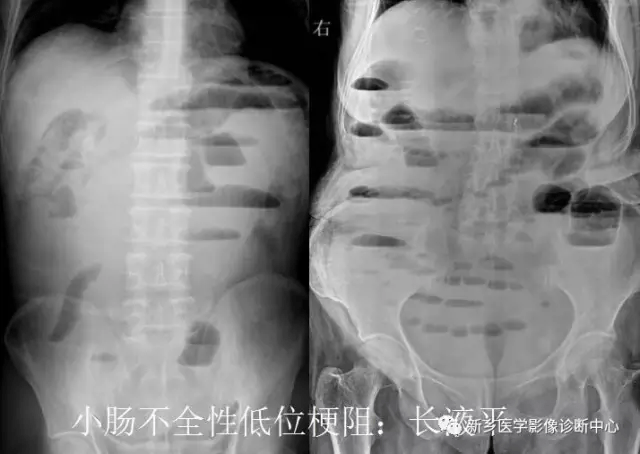

13 肠梗阻

文章图片